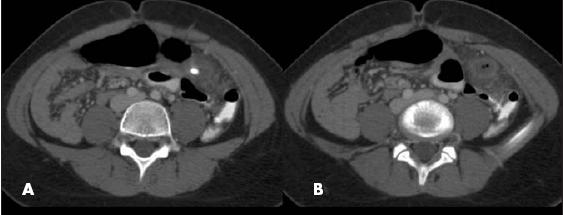

Axial CT images showed an appendicolith (A) and, 9 mm inferiorly, a tubular structure with intraluminal air and surrounding inflammatory changes in the left lower quadrant (B). These findings were consistent with appendicitis. Another view (C) showed that the superior mesenteric vein (SMV) (vertical arrow) joined with the splenic vein to form a portal confluence that rotated to the left of the superior mesenteric artery (SMA) (horizontal arrow). This finding was consistent with GI malrotation. The duodenal- jejunal junction was identified to the right of the vertebral column (not shown).

CT findings of acute appendicitis can include an enlarged caliber (greater than 6 mm in maximal transverse dimension), pericecal and periappendiceal inflammatory changes, phlegmon, extraluminal gas, and an appendicolith. 2 Congenital intestinal malrotation on CT can be determined by transposition of the SMA and SMV, with the SMA on the right side of the SMV, near its origin from the aorta.3